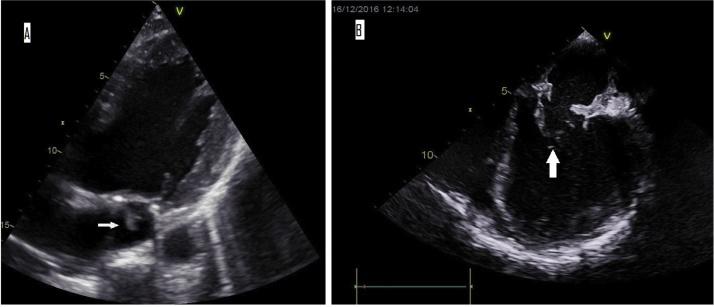

Invasive infections due to have rarely been described and mainly occur in immunocompromised individuals. We report a case of infective endocarditis caused by after previous cardiac surgery in a Lebanese patient with Marfan syndrome. We review the literature and conclude that this pathogen may be of particular medical relevance in the Mediterranean Basin.

由……引起的侵袭性感染鲜有报道,主要发生在免疫功能低下的个体中。我们报告了一例患有马凡综合征的黎巴嫩患者在先前心脏手术后由……引起的感染性心内膜炎病例。我们回顾了文献并得出结论,这种病原体在地中海盆地可能具有特殊的医学相关性。 (注:原文中“due to”和“caused by”后缺少具体病原体名称)